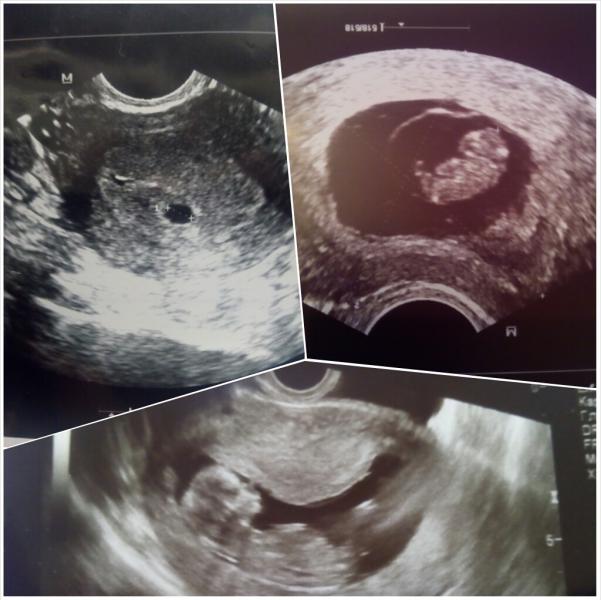

Время так быстро летит!)))

@christy2107 так, это было 20 января) где-то 8-9 недель! плод 1,9 мм)

Второе узи на какой неделе делали?)))

на 13 неделе уже?)))